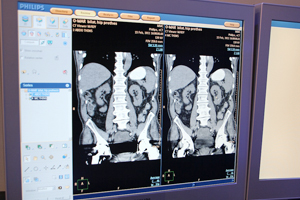

さらに,CTの新しい再構成法として,“O-MAR(Orthopedic Metal Artifact Reduction)”を紹介した。整形領域の人工骨頭などの金属アーチファクトを低減する再構成法である。人工骨頭などを埋め込んだ場合には,金属のメタルアーチファクトの影響で読影不可能なブラックエリアができるが,O-MARの再構成で金属アーチファクトを補正する。金属のアーチファクトを同定して,反復処理で計算することでエラーを除去する。CT画像の金属アーチファクトの除去は,Dual Energyで対応する方法があるが,O-MARではアルゴリズムで処理することでミドルクラスのCTでも搭載が可能で,ワンクリックで簡単に処理が行えることが特長だという。Ingenuity CTの新しいバージョンに搭載される予定だ。

![]() 金属アーチファクトを除去するO-MAR |